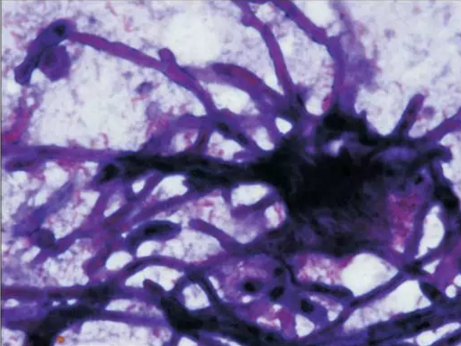

初步診斷為口腔毛霉菌病。取部分軟腭組織做病理學(xué)檢查。病理檢查顯示組織中含有大量無(wú)包膜的真菌、壞死血管組織,結(jié)果支持毛霉菌病的診斷。

3.png